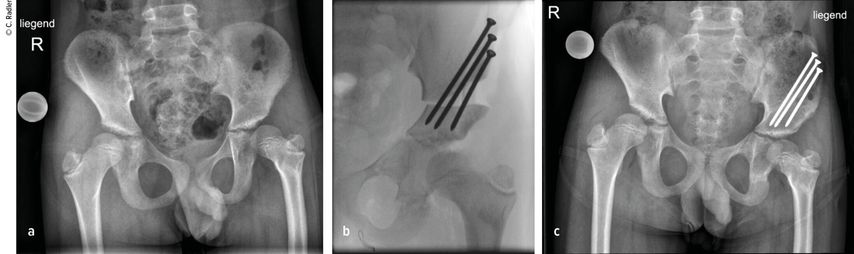

Der Typ 1B ist durch eine verzögerte Ossifikation/Pseudoarthrose subtrochantär oder im Schenkelhalsbereich charakterisiert, wobei auch ein kombinierter Typ mit Schenkelhals und subtrochantär verzögerter Ossifikation vorliegen kann. Klinisch imponiert neben der massiven Verkürzung die Außenrotations- und Beugekontraktur. In diesen Fällen ist eine komplexe Rekonstruktion, bestehend aus mehreren Schritten, erforderlich, die als Super-Hip-Operation subsumiert wird (Abb. 3).